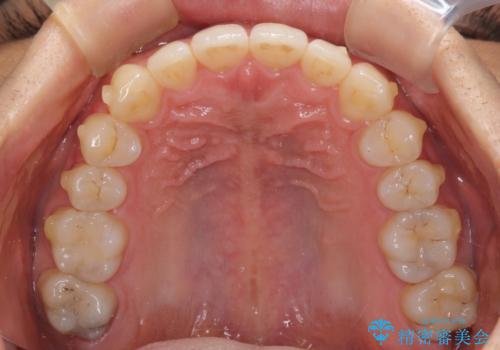

- 口元の突出感を治したいとのことで来院された患者様です。

上下顎ともにIPR(歯と歯の間を削る)と歯列全体の拡大によって口元が引っ込むように設計し、インビザラインにより治療を行うこととしました。

抜歯をして口元を下げなければならないほど出っ歯ではなかったため、少しずつ治療ゴールを変更しながら仕上げていきました。

気になっていた前歯の飛び出した印象は、最終的にはスッキリと引っ込み、大変満足していただきました。